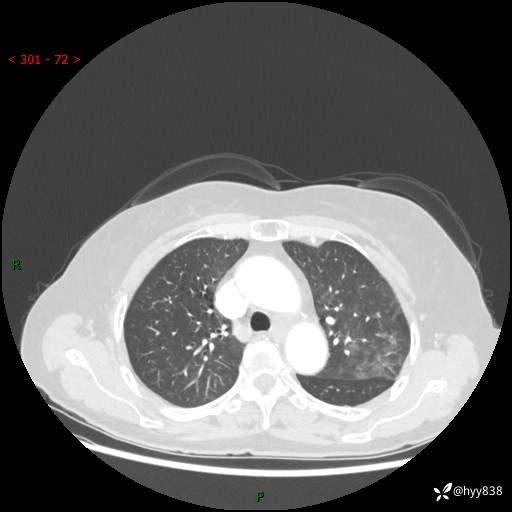

老年女性,偶然发现肺结节10天。结节不大,空洞不小,还牵拉胸膜---结果公布~

胸部CT增强(2024.8.2)